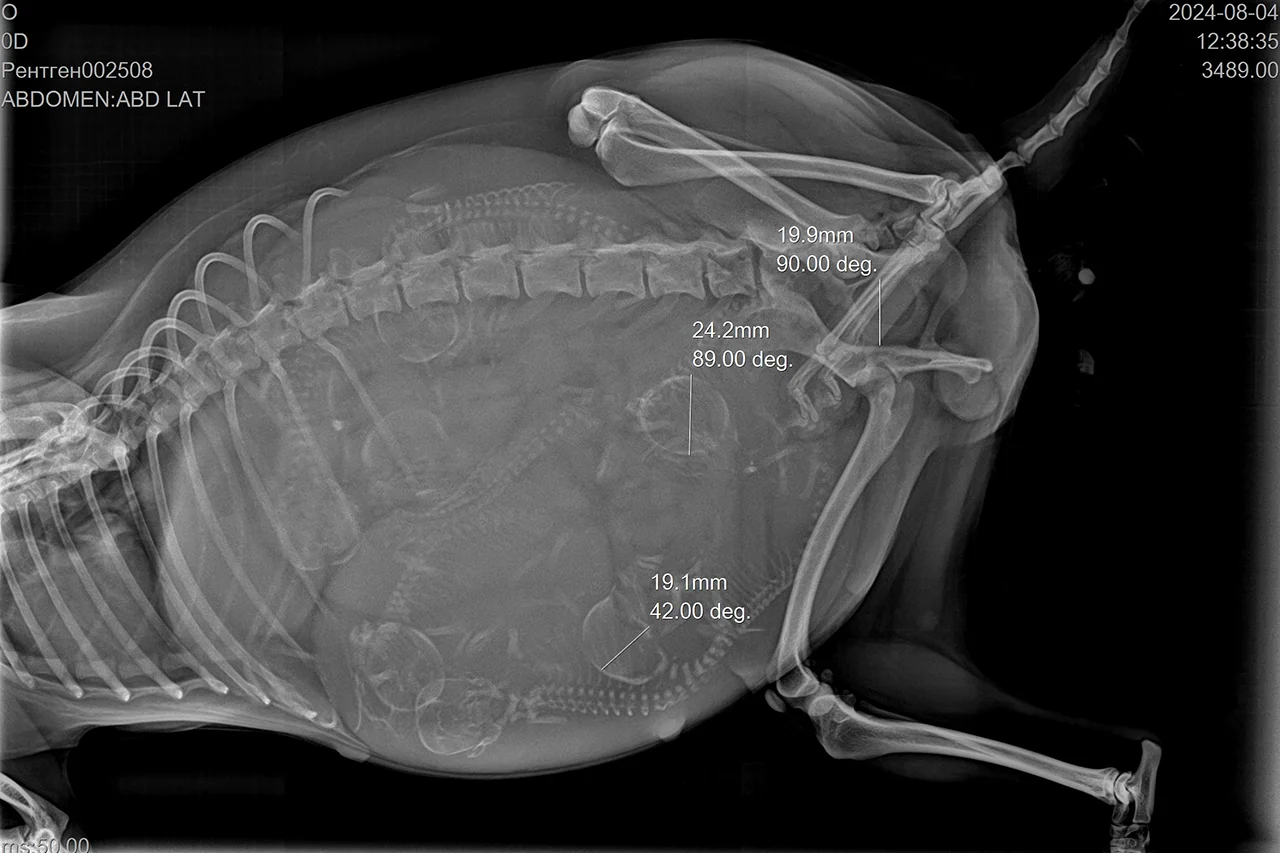

- С 25 дня после вязки можно посмотреть, произошло оплодотворение или нет. С этого времени можно увидеть сердцебиение у плодов и приблизительно сказать, сколько щенков ожидать. Конечно, это будет не точная цифра, потому что по ходу беременности ситуация может меняться. Нежизнеспособные эмбрионы в первом триместре могут рассосаться либо мумифицироваться, если это уже второй-третий триместр. Часто таскать беременную собаку на прием к врачу не стоит, чтобы не создавать ей лишний стресс. Кошек вообще везём в клинику только в экстренных случаях. Как я уже сказала, сделать УЗИ лучше на 25-й день, а потом за 2-3 недельки до родов на приеме мы просто смотрим, в каком состоянии мама, беспокоит её что-то или нет, сохранились ли плоды, всё ли с ними нормально. До родов маме лучше проконтролировать электролитный состав крови и кальций, поскольку у беременных он расходуется быстро, а во время родов просто необходим. Хорошо бы сделать и общий анализ крови, чтобы посмотреть, нет ли у животного анемии. Повторно делаем УЗИ брюшной полости за 3−4 дня до родов. Хорошо, если хозяева точно знают (хотя бы плюс-минус один день), когда животному рожать. У собак это 62-63-й день после вязки, у кошек – 63−65-й день. В идеале на 58−59 день беременности делается рентген, чтобы точно знать, сколько малышей ожидать.

- Это раньше думали, что ультразвуковые лучи негативно влияют на плод. Но нет. А вот то, что мы едим разную ерунду, влияет гораздо больше на всех нас. Но по УЗИ определить точное количество плодов мы не можем, в отличие от рентгена. А это необходимо, чтобы владелец питомца мог понять, когда закончились роды. По рентгену также можно посмотреть размер головы плода, пройдет ли он через таз мамы. Это один из методов понять, сможет ли она родить сама или нет. Есть породы, которые сами разродиться не могут. У собак это в первую очередь все брахицефалы: мопсы, французские и английские бульдоги. В 90% их случай – это кесарево. Вообще сейчас выведено много пород, которые сами не могут родить: стандартно это мелкие собачки. Шпицы сами рожают не всегда, часто кесарят карликовых такс – там уже 50 на 50%. Но у меня был случай, когда карликовая такса разродилась сама без проблем.